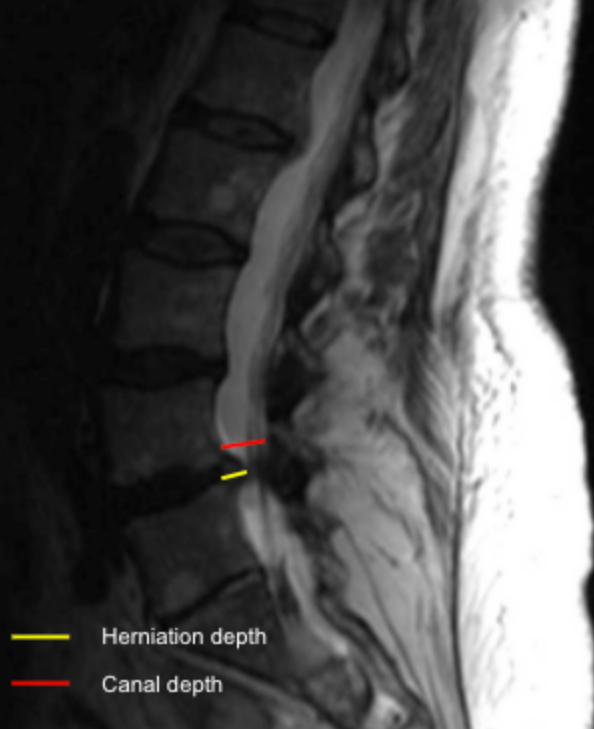

Image Type Lumbar Spine X-Ray CT Scan MRI Scan Anteroposterior (AP) Canal Diameter Cauda Equina Nerve Root Area Conus Medullaris Level Cross-Sectional Area (CSA) of Spinal Canal Disc-Height Index (DHI) Disc Herniation Size Disc Herniation Types Dural Sac CSA Epidural Fat Thickness Filum Terminale Thickness Foraminal Height and Width High-intensity Zone (HIZ) Lateral Recess Width/Depth Modic Endplate Changes (Type I, II, III) Modic (Marrow Signal) Changes Pfirrmann Classification (I-V) Vertebral Bone Quality (VBQ) Score Vertebral Endplate Defects